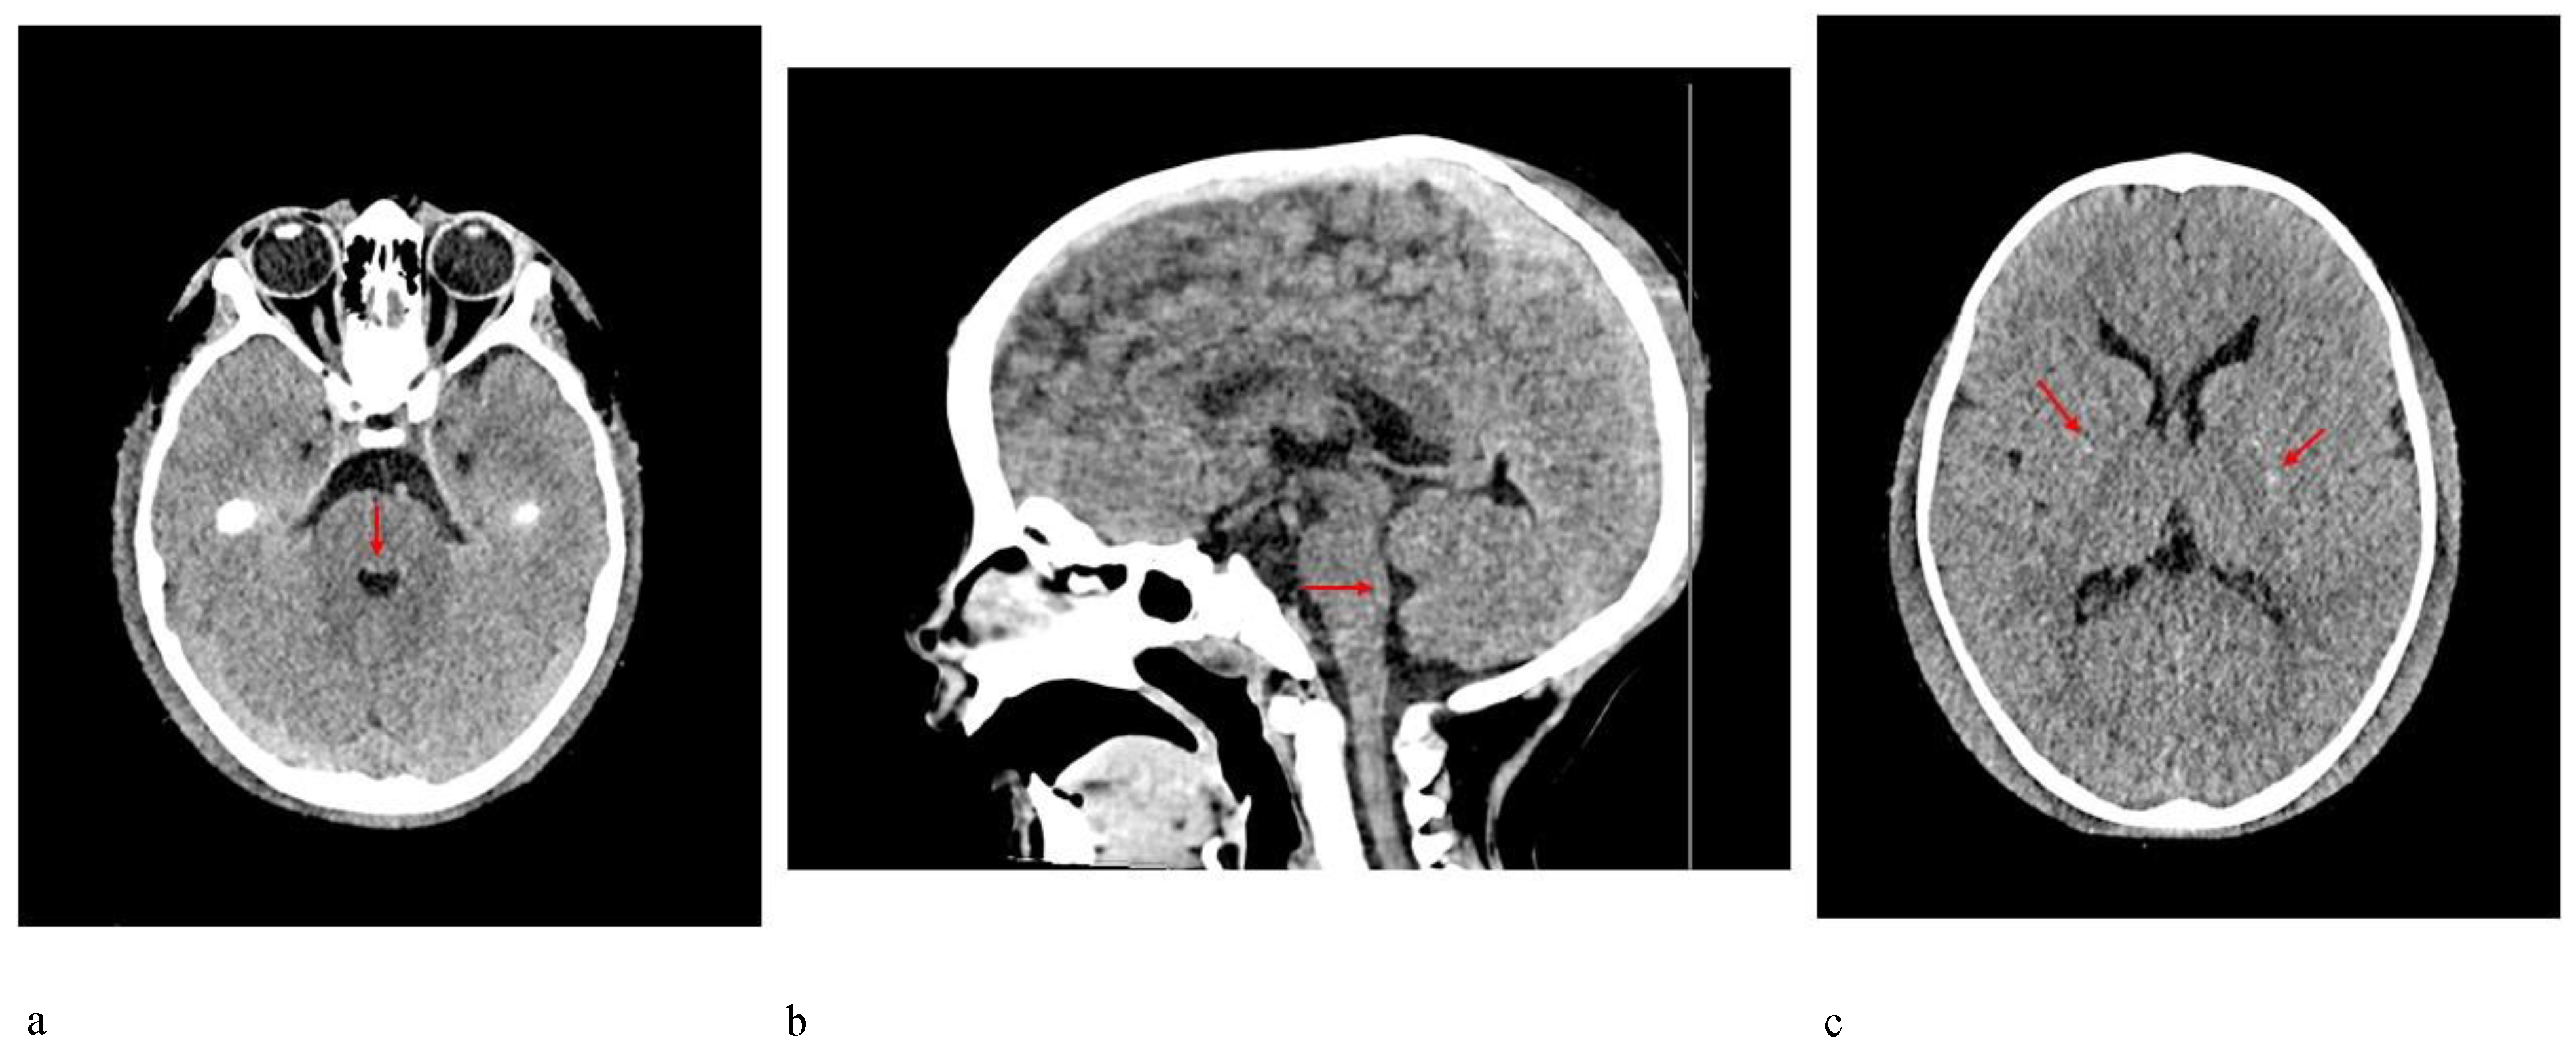

Patient 2 was a 3-year-old boy referred to our hospital because of macrocephaly and frontal painful edema. The child was a full-term male born to unrelated parents. His parents reported an accidental cranial trauma one month before hospitalization, followed by an increase in head circumference some days later and subsequently an initial painful soft mass in the eyelid region. Suspecting urticaria/angioedema due to an insect bite, oral therapy with cetirizine and betamethasone was started without improvement. Because of worsening clinical signs, the patient was admitted to our hospital, where facial painful lesions and macrocephaly were evidenced (occipital-frontal circumference 54 cm, >95th percentile). Blood analysis and urinalysis, assessment of the tumor markers CEA and alpha-fetoprotein, autoimmunity tests and infective screening were performed, all within the normal range, except for an elevated C-reactive protein (CRP) value of 52.76 mg/L (normal range 0–5 mg/L). Cardiologic, neurologic, onco-hematologic, otorhinolaryngologic, and ophthalmic assessments did not reveal any note worthy alterations. A cerebral computed tomography (CT) scan showed the presence of pericranial soft tissue swelling and edema surrounding the cranial bone, prominence of vascular structures, small areas of heterotopic calcifications in the lenticular nuclei, bilateral thickening of the optic nerves, pontine dysmorphism with bulging of the dorsal surface and enlargement of the subarachnoid cisterns anteriorly to brainstem (Figure 4). During hospitalization, the patient continued oral therapy with cetirizine and betamethasone with progressive edema reduction. Several weeks later, a small soft mass appeared in the left cervical region, which progressively expanded to the scapular region and was associated with pain and limited neck motion. Doppler ultrasound examination indicated moderate thickening of all muscles of the posterior cervical and dorsal region (particularly on the left side), characterized by heterogeneous internal echogenicity but without fibrillar structure alterations, and a significant increase in vascularization. Brain MRI revealed pontine dysmorphism with fusion of the facial colliculi and bulging of the dorsal surface protruding into the fourth ventricle, determining a reduction of its dimension; thickened inferior cerebellar peduncles; squared frontal horns; and mild ectasia of the Virchow-Robin spaces, cisterns, and subarachnoid spaces. It also showed remarkable T2/FLAIR hyperintensity in the bilateral dentate nuclei and the adjacent peridentate area of white matter (Figure 5). STIR-coronal and postcontrast T1 MRI of the cervicothoracic region showed a diffuse hyperintense signal and contrast enhancement extending along the muscles and fascial planes of the neck and thoracic wall (Figure 6). Cranial and facial edema progressively extended down the neck, producing a latero-cervical hard swelling, further expanding to the dorsal region in the sub-scapular area. Genetic counseling raveled the presence of a proximal implant of the big toe, shorter than the second toe and with bilateral valgus deviation, in addition to the neck and dorsal lesions. A diagnosis of FOP was hypothesized. Molecular analysis of DNA from a peripheral blood sample identified a de novo heterozygous mutation in the ACVR1/ALK2 gene (c.617A>G, p.R206H), confirming the clinical suspicion.

Imaging contributes greatly to FOP diagnosis. Whereas MRI systemic findings, including muscle and skeleton features, are well-known, CNS MRI findings are less recognized, especially in childhood [11,12,13]. Patient 2 in the present report received a CNS MRI assessment, revealing a pontine anomaly and fusion of the facial colliculi, determining a reduction of the fourth ventricle’s dimension, thickened inferior cerebellar peduncles, squared frontal horns, and mild ectasia of the Virchow–Robin and subarachnoid spaces. The assessment also showed remarkable T2/FLAIR hyperintensity, in bilateral dentate nuclei and the adjacent cerebellar white matter (see Figure 4). In 2012, Kan et al. [12] described CNS MRI findings of four patients (two adults and two children), detecting extensive hyperintense lesions in the cerebral white matter, the spinal cord, the dorsal pons and the dentate nuclei bilaterally and surrounding the fourth ventricle. These findings were similar to those described in patient 2. Furthermore, similar lesions with demyelination and focal inflammatory changes were also consistently observed in two transgenic knock-in mouse models, suggesting that dysregulated BMP signaling disturbs the normal homeostasis of target tissues, including the CNS. On the other hand, Severino et al. [10] performed an observational cross-sectional brain MRI study in 13 patients and evidenced that all patients presented small asymptomatic lesions resembling hamartomas at the level of the dorsal medulla and ventral pons, which were associated with minor brainstem dysmorphisms and other CNS abnormalities. Patient 2 had similar pons lesions, resembling hamartomas. Furthermore, he did not present any clinical CNS signs/symptoms to date. These observations further support the hypothesis that the effects of mutations of the ACVR1/ALK2 gene also extend to the CNS, and these CNS lesions could be considered a benign process, because of the absence of corresponding clinical symptoms.

Figure 4. CT scan of the brain of patient 2 showing (a,b) dysmorphism of the pons with bulging of the dorsal surface (arrows), (c) small areas of mineralization at the level of lenticular nuclei (arrows); pericranial soft tissue swelling and edema surrounding cranial bone are also evident in all 3 images.